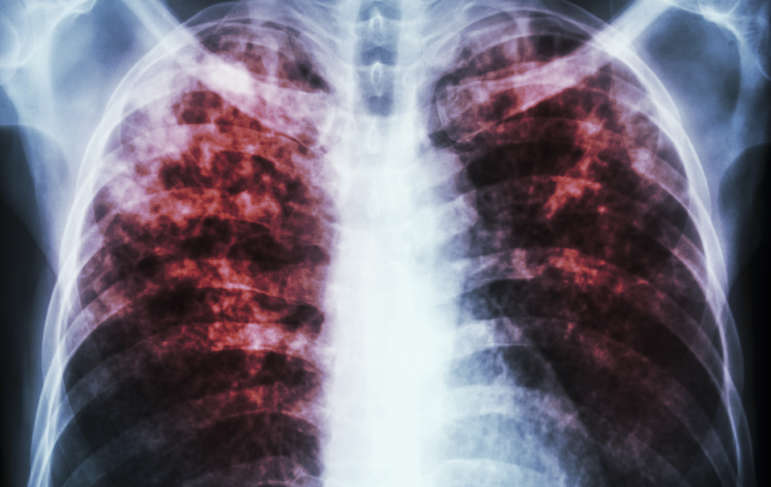

Mesothelioma is a devastating cancer that is caused primarily by asbestos exposure. It is a terrible diagnosis to receive and not many people know what it is, which is why mesothelioma awareness is so important. Many people’s lives could be saved and could be improved if more people knew about the disease and its causes. With COVID-19 affecting the world, it is hard to raise awareness and show support for the ones we love who are affected by mesothelioma. Since we cannot gather, we need to find other ways that we can show support and raise awareness for the cancer.